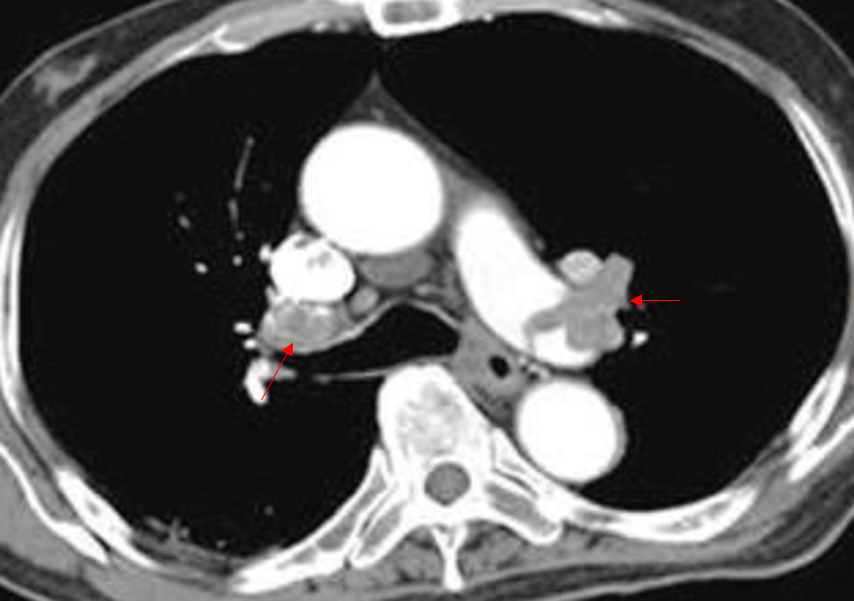

Img | CT: Massive thrombosis at both main pulmonary arteries |

• CT상 양쪽 pulmonary artery에 massive PTE가 확인된다. 현재 SLE로 치료 중인데, antiphospholipid Ab가 확인된다. SLE의 합병증으로 APS가 발생할 수 있다. Thrombotic event가 있으면서 antiphospholipid Ab가 2회 연속으로 검출될 때 APS로 진단할 수 있다.